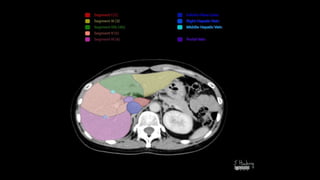

SEGMENTAL ANATOMY OF LIVER

• The French surgeon and anatomist Claude Couinaud divided the liver

into eight functionally independent segments

• allows resection of segments without damaging other segments.

• Each segment has its own vascular inflow, outflow and biliary

drainage.

• In the centre of each segment there is a branch of the portal vein,

hepatic artery and bile duct.

• In the periphery of each segment there is vascular outflow through

the hepatic veins.

• Liver is divided into a functional

left and right liver by a main

scissurae containing the middle

hepatic vein.

• This is known as Cantlie's line.

• Cantlie's line runs from the

middle of the gallbladder fossa

anteriorly to the inferior vena

cava posteriorly.

• Right hepatic vein divides the

right lobe into anterior and

posterior segments.

• Left hepatic vein divides the left

lobe into left medial and left

lateral sections.

• The portal vein divides the liver

horizontally into upper and lower

segments.

• There are eight liver segments.

• Segment IV is divided into segment IVa and IVb according to Bismuth.

• The numbering of the segments is in a clockwise manner.

• Segment I (the caudate lobe) is located posteriorly.

• It is not visible on a frontal view.